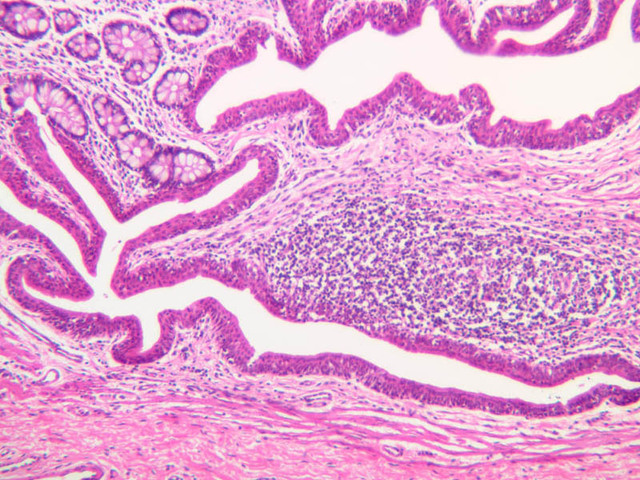

Continuous capillaries consist of a sheet of endothelial cells that, as the name implies, has no defects or discontinuities. Fenestrated capillaries have areas of fusion of plasmalemmae that are responsible for enhanced transport as in kidney and endocrine organs. Discontinuous capillaries, or sinusoids, have gaps between individual endothelial cells. Sinusoids of the liver and spleen are examples. Sinusoids, which occur in some organs as branches directly from arterioles (in place of capillaries) also consist of a single layer of endothelial cells, but are two to three times greater in diameter and more irregular in shape than capillaries. Many of the cells lining sinusoids have phagocytic capabilities (e.g. Kupffer cells of the liver). Venules, the vessels into which capillaries or sinusoids feed and the smallest vessels of the venous system are endothelial tubes, larger in diameter than capillaries, surrounded by a thin sheath of connective tissue cells and fibers. When venules reach a diameter of about 40 μmμ, smooth muscle cells appear, but do not form a distinct layer. Look for arterioles, capillaries, and venules in slides B-12 (jejunum, H&E [10x, 20x, 40x-labeled] [2.5x, 10x, 20x, 40x]), B-13 (jejunum, PAS [2.5x, 10x, 20x-labeled, 40x]), B-15 (jejunum, H&E [2.5x, 10x, 20x, 40x] [2.5x, 10x, 20x, 40x] [10x, 20x, 40x]), B-16 (ileum, H&E [10x, 20x, 40x-labeled] [2.5x, 10x, 20x, 40x]), B-23 (colon, H&E [2.5x, 10x, 20x-labeled, 40x]), B-24 (colon, H&E [2.5x, 10x, 20x, 40x-labeled]), B-26 (rectal-anal junction, H&E [2.5x, 10x, 20x, 40x] [2.5x, 10x, 20x, 40x-labeled]). Capillaries and venules may be distinguished from small lymph vessels, also present, by the fact that the blood vessels contain red blood cells while the lymph vessels do not. Study a number of examples of each kind of small vessel, looking for the changes that characterize arterioles as they get smaller and venules as they get larger. Be able to distinguish differences between capillaries and the smallest arterioles and venules. Look for additional examples of small vessels of the various kinds in the dense connective tissue of skin (A-48, abdominal [2.5x, 10x, 20x, 40x]; A-50, fingertip [2.5x, 10x, 20x, 40x] [2.5x, 10x, 20x, 40x] [2.5x, 10x, 20x, 40x]; A-58, axillary [2.5x, 10x, 20x, 40x-labeled]), using care not to confuse the cross-sections of glands (which consist almost entirely of epithelial cells) with blood vessels. Arterioles, especially, are cut in different planes and are not always easy to identify.

B12, Jejunum, 10x (H&E) B12, Jejunum, 20x (H&E) B12, Jejunum, 40x Labeled (H&E) B12, Jejunum, 2.5x (H&E) B12, Jejunum, 10x (H&E) B12, Jejunum, 20x (H&E) B12, Jejunum, 40x (H&E) B13, Jejunum, 2.5x (PAS) B13, Jejunum, 10x (PAS) B13, Jejunum, 20x Labeled (PAS) B13, Jejunum, 40x (PAS) B15, Jejunum, 2.5x (H&E) B15, Jejunum, 10x (H&E) B15, Jejunum, 20x (H&E) B15, Jejunum, 40x (H&E) B15, Jejunum, 2.5x (H&E) B15, Jejunum, 10x (H&E) B15, Jejunum, 20x (H&E) B15, Jejunum, 40x (H&E) B15, Jejunum, 10x (H&E) B15, Jejunum, 20x (H&E) B15, Jejunum, 40x (H&E) B16, Ileum, 10x (H&E) B16, Ileum, 20x (H&E) B16, Ileum, 40x Labeled (H&E) B16, Ileum, 2.5x (H&E) B16, Ileum, 10x (H&E) B16, Ileum, 20x (H&E) B16, Ileum, 40x (H&E) B23, Colon, 2.5x (H&E) B23, Colon, 10x (H&E) B23, Colon, 20x Labeled (H&E) B23, Colon, 40x (H&E) B24, Colon, 2.5x (H&E) B24, Colon, 10x (H&E) B24, Colon, 20x (H&E) B24, Colon, 40x Labeled (H&E) B26, Rectal-Anal Junction, 2.5x (H&E) B26, Rectal-Anal Junction, 10x (H&E) B26, Rectal-Anal Junction, 20x (H&E) B26, Rectal-Anal Junction, 40x (H&E) B26, Rectal-Anal Junction, 2.5x (H&E) B26, Rectal-Anal Junction, 10x (H&E) B26, Rectal-Anal Junction, 20x (H&E) B26, Rectal-Anal Junction, 40x Labeled (H&E) A48, Abdominal Skin, 2.5x (H&E) A48, Abdominal Skin, 10x (H&E) A48, Abdominal Skin, 20x (H&E) A48, Abdominal Skin, 40x (H&E) A50, Fingertip, 2.5x (H&E) A50, Fingertip, 10x (H&E) A50, Fingertip, 20x (H&E) A50, Fingertip, 40x (H&E) A50, Fingertip, 2.5x (H&E) A50, Fingertip, 10x (H&E) A50, Fingertip, 20x (H&E) A50, Fingertip, 40x (H&E) A50, Fingertip, 2.5x (H&E) A50, Fingertip, 10x (H&E) A50, Fingertip, 20x (H&E) A50, Fingertip, 40x (H&E) A58, Axillary Skin, 2.5x (H&E) A58, Axillary Skin, 10x (H&E) A58, Axillary Skin, 20x (H&E) A58, Axillary Skin, 40x Labeled (H&E) B29, Liver (Sinusoids), 10x (H&E) B29, Liver (Sinusoids), 20x (H&E) B29, Liver (Sinusoids), 40x (H&E) B29, Liver (Sinusoids), 10x Labeled (H&E) B29, Liver (Sinusoids), 20x (H&E) B29, Liver (Sinusoids), 40x Labeled (H&E) B30, Liver (Sinusoids), 10x (H&E) B30, Liver (Sinusoids), 20x (H&E) B30, Liver (Sinusoids), 40x (H&E) B35, Liver (Sinusoids), 10x (PAS) B35, Liver (Sinusoids), 20x (PAS) B35, Liver (Sinusoids), 40x (PAS)